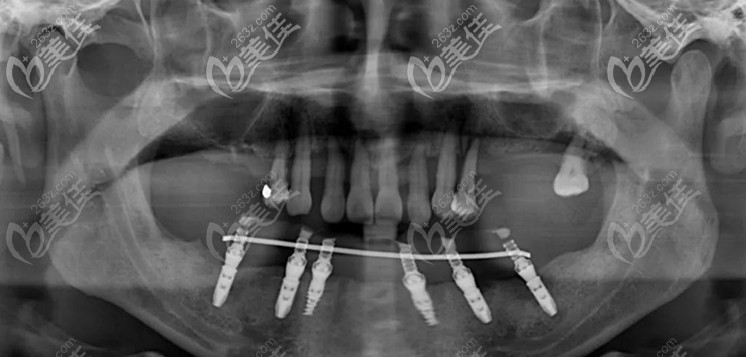

▲下颌的6颗即刻种植牙

第二次在进行上半口的上颌穿翼板VIIV即刻种植技术,整个手术进行了2个多小时,在周院长和蒋院长的配合下,6颗植体都按照既定设计方案植入骨内。

▲上半口两颗倾斜的植体就是穿翼板种植技术

其中有2颗是高难度的穿翼板植体,避开了错综复杂的神经血管,此技术不植骨、不等待、出血量少,突破了传统种植牙对牙槽骨条件的限制。